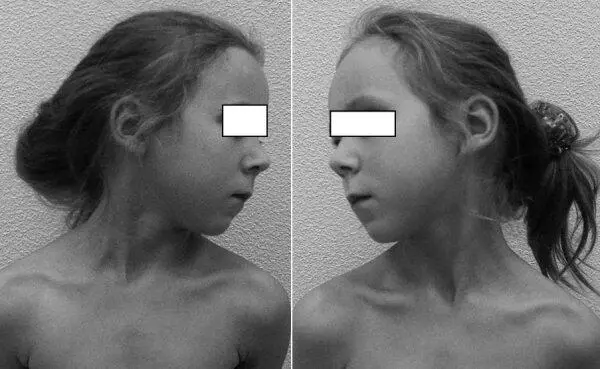

На функциональных КТ движения в CI–CII отсутствовали при фиксированном латеральном подвывихе атланта (рис. 6.17). Голова была в типичном положении «верхней» кривошеи – со смещением вперед и в сторону (рис. 6.18).

Рис. 6.18.Кривошея у пациентки 12лет с хроническим атланто-аксиальным блокированием